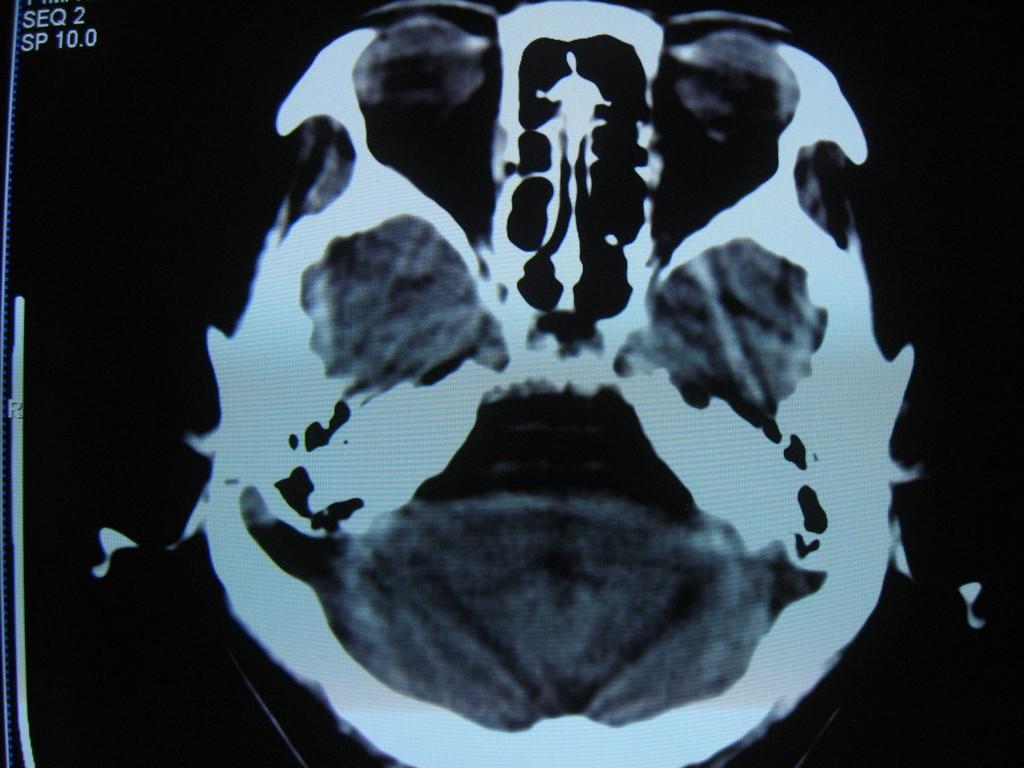

中老年女性病人,头晕头疼做ct,发现右侧乙状窦路径上低密度影,邻近颅骨变薄,ct值见图像上标注,我考虑:1、表皮样囊肿或蛛网膜囊肿。2、乙状窦变异。请问对吗?  乳突导静脉没有考虑,主要是因为向颅底层面扫了几层没有发现右侧颞枕骨骨质完整,没有发现导静脉压迹,欢迎讨论。

1)右侧乙状窦前移。2)右侧乙状窦区皮样囊肿或表皮样囊肿待排;建议行mri检查。

右侧乙状窦前移。2)右侧乙状窦区皮样囊肿或表皮样囊肿